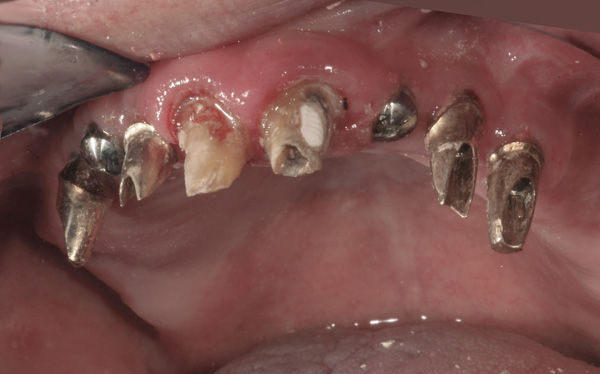

Background: In this case, the patient had a failing mandibular and maxillary dentition due to caries secondary to radiation-induced xerostomia. The patient had had a radical neck dissection to remove a squamous cell carcinoma of the throat 9 years prior to his prosthodontic consultation with the authors. The patient reported a history of radiation therapy following surgery, but did not have a shielding stent. A staged approach was used so as to avoid removable prosthetics on his severely dry soft tissues. He chose to treat his mandibular issues first. Figure 9 shows healing abutments next to the temporarily retained natural teeth, and Figure 10 shows the first-stage custom abutments inserted with relatively good gingival contour and no recession. Recession was clearly seen around all first-stage abutments following adjacent extractions and second-stage implant placement (Figure 11).

Figure 9 Healing abutments.

Figure 9

Figure 10  First-stage custom abutments.

Figure 10

Figure 11 Recession evident around first-stage abutments following adjacent extractions and second-stage implant placement.

Figure 11